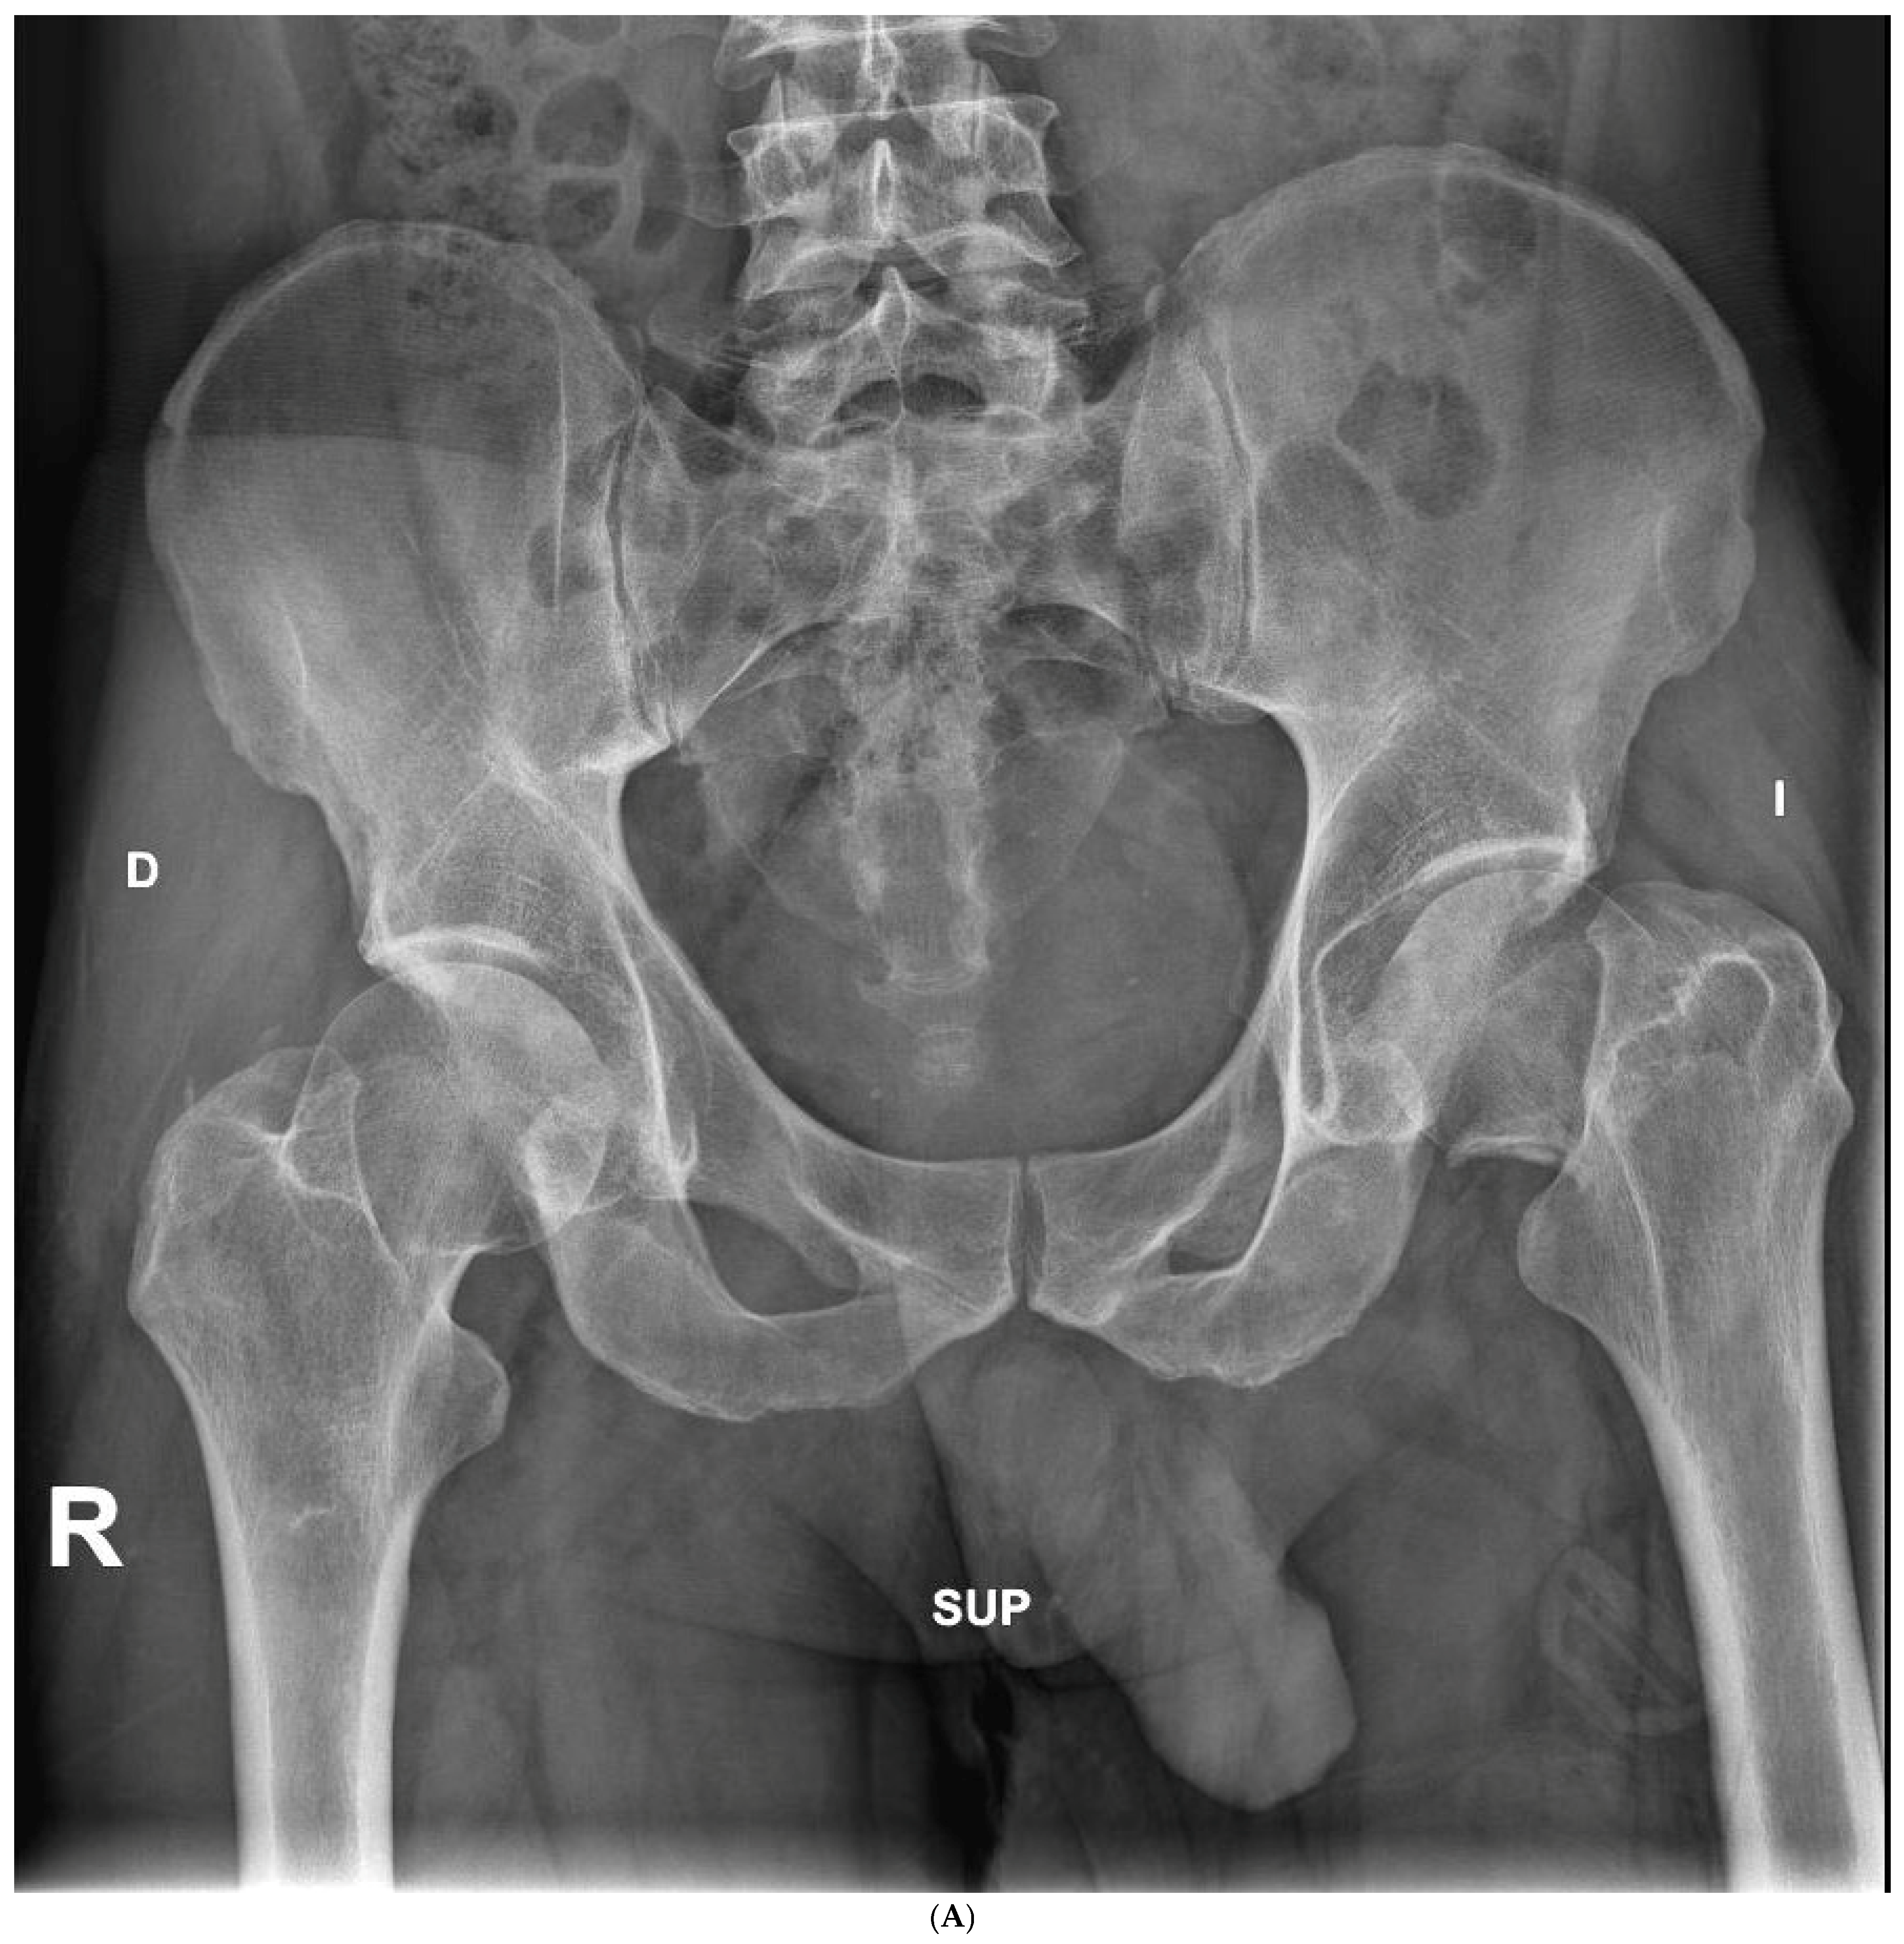

Figure 3.

(A) Preoperative anteroposterior X-ray. Left hip sustained a displaced femoral neck fracture. (B) Postoperative anteroposterior X-ray (SFS group). Both the short stem and acetabular cup appear well osseointegrated and stable at final follow-up. (C) Postoperative lateral X-ray (SFS group). The stem is osseointegrated and there is absence of radiolucent lines at bone-implant interface.